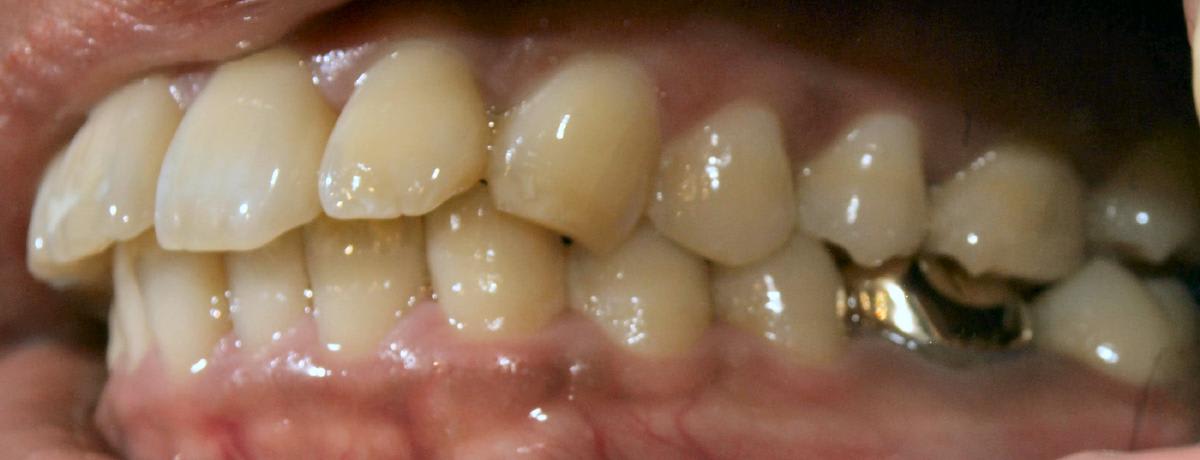

ce cas est tres simple , l'usure des canines est due à la couronne en metal . tu l'enleves ,tu lui fais un prov , et on en parle plus . ç est 1 pb de décalage latéral en OIM .

tu remarqueras que les 2 canines sont usées de façons différentes .

celle de droite est 1 usure par mouvement de grande amplitude alors que celle de gauche ,non .

et comme par hasard , ç est celle de droite qui est usée par le + grand mouvement , comme pour s'ecarter le plus possible de la 36 .

pas pour rien ,non plus que dans les cas ( comme le tient) d'occlusion inverse postérieur bilatérale ,elles sont sorties et assez longues . ç est pour laisser aux molaires le temps de guider latéralement la mand lors de la fermeture .

Mais mais mais , si tu perturbes le trajet d'entrée de fermeture par une couronne iatrogène , qui modifie cet équilibre instable en latéral , 1 des canines se trouvera en sur verrouillage ( ta 43 ? ) et l'autre en sur guidage ( ta 33 ?) .

Pourtant j'ai l'impression (mais je dois etre idiot) que sur les cliches les dents s'engrainent relativement bien sans inversé ou bout a bout molaire...

Les milieux interincisifs sont centres, les 6 max sont recouvrent bien en vestibulaire les 6 du bas... Ou est le decalage?

Ah ok maintenant je vois! Mais c'est plus 37 et 47 qui sont en vestibuloposition non?